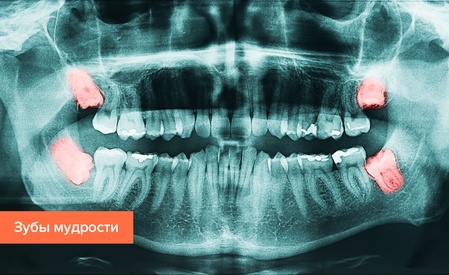

«Зуб мудрости» — третий крайний моляр, имеющий от трех до пяти корней. По строению он ничем не отличается от «соседей». На вопрос «Сколько зубов мудрости у человека?» нельзя ответить однозначно. Прорезываются они примерно к двадцати годам, по одному с каждой стороны обеих челюстей. Однако существуют люди и без «зубов мудрости». Это вариант нормы, поскольку в процессе эволюции человека необходимость в «восьмерке» отпала, и строение челюстей претерпело соответствующие изменения. На сегодняшний день третьи моляры считаются рудиментарным органом.